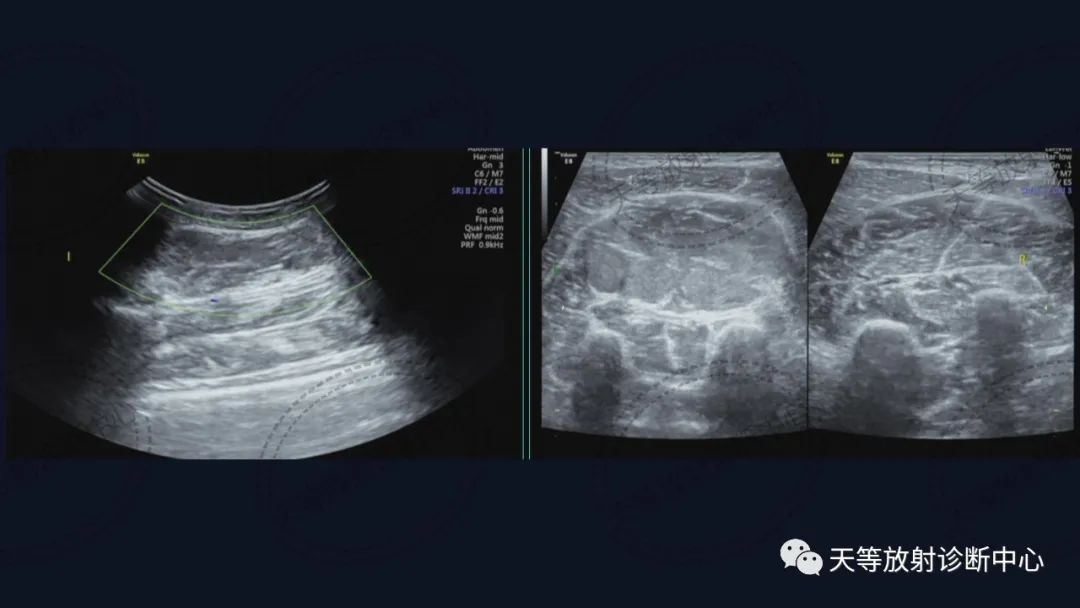

上图:DWI呈明显高信号影。

T1WI肿块边缘见环状高信号影,考虑出血信号。

前后两次对比观察,病灶略有增大。